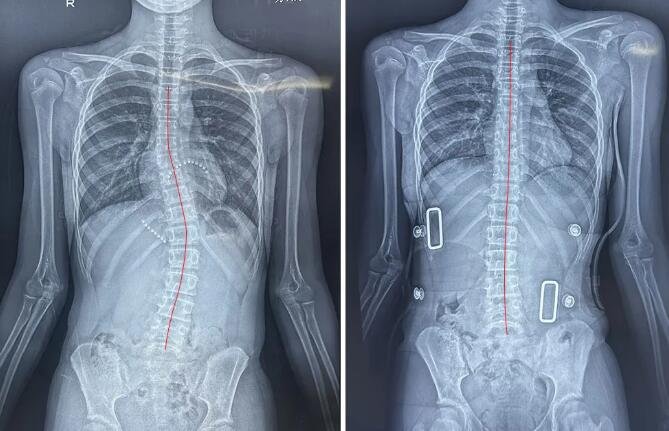

青春期女生调整前(左图)、8节调整课后(右图)

13岁少年脊柱形态调整前(左图)、1个月调整课后(右图)